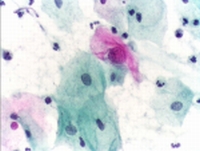

Το τεστ Παπανικολάου (PapTest) είναι μια απλή ανώδυνη εξέταση κατά την οποία εξετάζονται τα επιθηλιακά κύτταρα που λαμβάνονται από τον τράχηλο της μήτρας αν παρουσιάζουν αλλοιώσεις ύποπτες για νεοπλασία (καρκίνο τραχήλου της μήτρας).

Παθολογικό τεστ Παπανικολάου Ανάλογα με το βαθμό και την σοβαρότητα των αλλοιώσεων η γυναίκα παραπέμπεται μετά την εξέταση σε επέμβαση κολποσκόπησης και βιοψίας του τραχήλου. Ο κυριότερος παράγων κινδύνου για την ανάπτυξη καρκίνου τραχήλου της μήτρας είναι η φλεγμονή που προκαλείται από τους διάφορους τύπους του ιού των ανθρώπινων θηλωμάτων (HPV-human papilloma virus) με το οποίον οι γυναίκες μολύνονται με τη σεξουαλική επαφή. Υπάρχουν περισσότεροι από 100 ορότυποι του ιού HPV. Οι ορότυποι 16 και 18 του ιού προκαλούν το 70% των καρκίνων του τραχήλου της μήτρας. Για την πρόληψη της λοίμωξης σήμερα υπάρχουν 2 εμβόλια που γίνονται προληπτικά σε κορίτσια ηλικίας 12-15 ετών αλλά και σε κορίτσια ηλικίας 15-26 ετών εάν δεν έχουν εμβολιαστεί στη συνιστώμενη ηλικία.